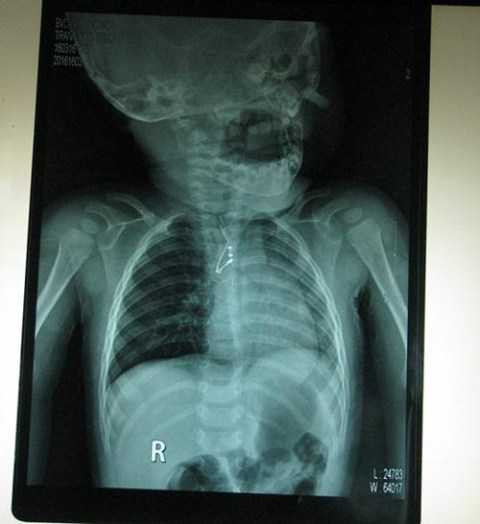

| Sau khi chụp Xquang, các bác sỹ đã phát hiện ra một tụ điện trở kim loại trong phế quản cháu bé. |

Sau khi chụp Xquang, các bác sỹ phát hiện ra một dị vật nằm ở phế quản góc phải nên đã chuyển bệnh nhi qua khoa Tai - Mũi - Họng. Đến sáng 17/3, bé T. được gây mê nội soi khí phế quản. Sau đó, các bác sĩ lấy ra từ phế quản bệnh nhi này một dị vật là tụ điện tử dài trên 2cm.